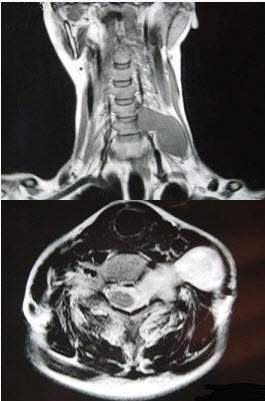

- 单项选择题52岁女性患者,左颈部无痛性包块渐进性增大,MRI检查如图,应考虑为()。

A、左侧颈部神经鞘瘤

B、左侧颈部神经纤维瘤

C、左侧颈部动脉瘤

D、左侧颈部转移癌

E、左侧颈部脂肪瘤

- A